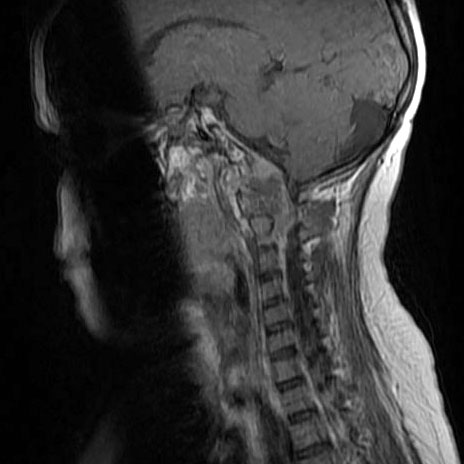

骶骨脊索瘤怎么治疗好?骶骨脊索瘤属于脊索瘤的一类,脊索瘤起源于胚胎脊索残留物,一百万人中大概会出现一例,而其中50%是骶骨脊索瘤患者,骶骨脊索瘤是骶骨较常见的恶性肿瘤,...

脊索瘤 是由胚胎脊索残留沿着神经轴的长度在发育活跃的部位产生的一种肿瘤。脊索瘤可能发生在脊柱的任何地方。它较常出现在尾骨附近(称为骶骨肿瘤)或脊柱与头骨(称为斜坡肿瘤...